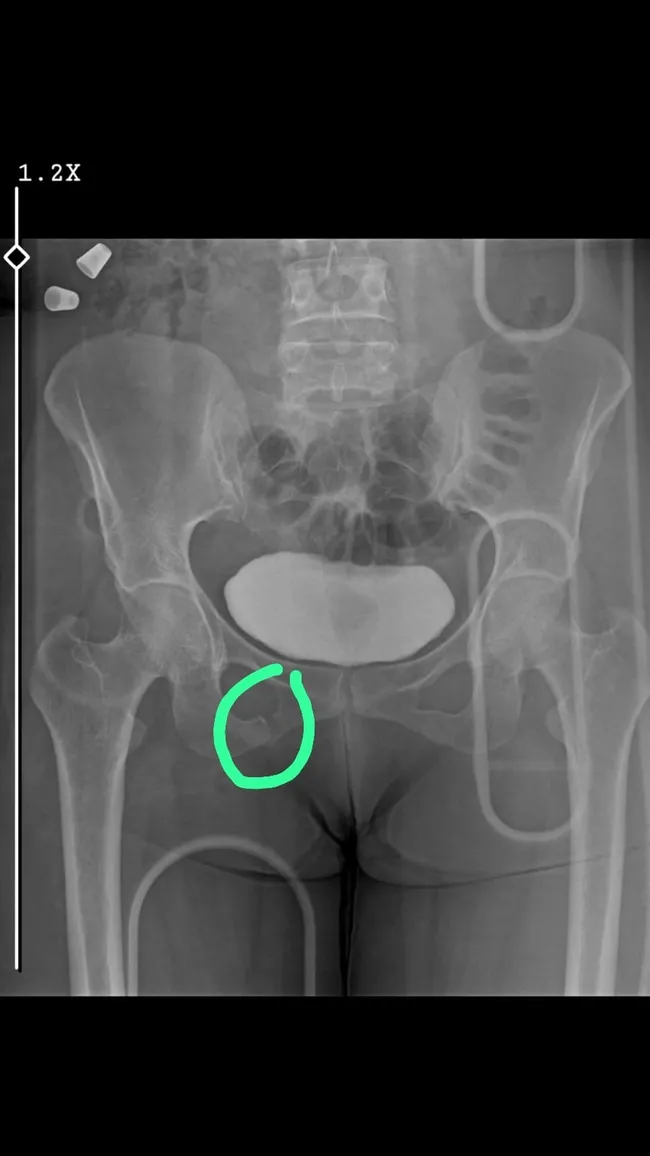

İslâhiye ilçesinde 20 Temmuz gecesi gerçekleşen kazada, Ahmet Hakan A. yönetimindeki 44 AFG 537 plakalı otomobil, V.Ö. idaresindeki 46 AHZ 938 motosiklete çarptı. Çarpmanın etkisiyle devrilen motosikletteki Mehtap Gülşen ağır yaralandı. Otomobil sürücüsü olay yerinden kaçarken, 112 Acil Sağlık ekipleri tarafından İslâhiye Devlet Hastanesi'ne kaldırılan Gülşen'in kalça kemiğinin kırıldığı belirlendi. Ameliyata alınan Gülşen, tedavisinin ardından taburcu oldu.

İslâhiye ilçesinde 20 Temmuz gecesi gerçekleşen kazada, Ahmet Hakan A. yönetimindeki 44 AFG 537 plakalı otomobil, V.Ö. idaresindeki 46 AHZ 938 motosiklete çarptı. Çarpmanın etkisiyle devrilen motosikletteki Mehtap Gülşen ağır yaralandı. Otomobil sürücüsü olay yerinden kaçarken, 112 Acil Sağlık ekipleri tarafından İslâhiye Devlet Hastanesi'ne kaldırılan Gülşen'in kalça kemiğinin kırıldığı belirlendi. Ameliyata alınan Gülşen, tedavisinin ardından […]